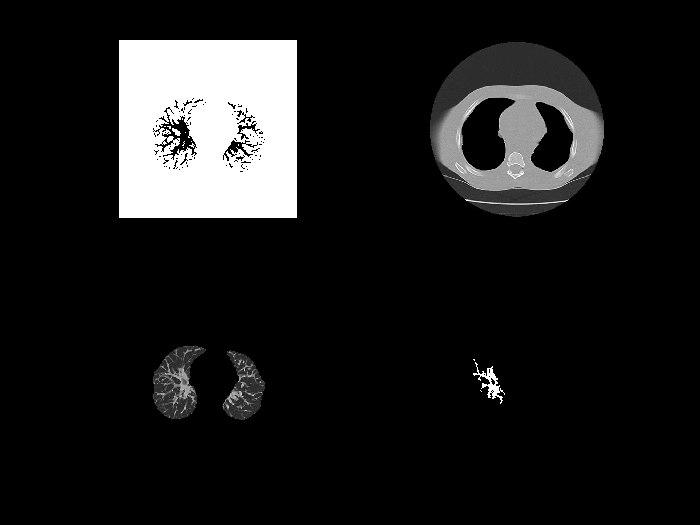

subplot(2,2,1);imshow(lg),title('肺血管'); %保持原图,显示图像g

采用阈值处理方法提取出感兴趣区域(对于手动进行直方图分析时,默认选取双峰间谷底对应的灰度级作为分割门槛),通过上述方法进行图像分割后,在形态学上能够清晰地区分出肺部血管与肺实质之间的界限。尽管该方法存在一定的误差范围,在实际应用中用于检测血管内是否存在血栓时仍需谨慎评估其准确性。

- 区域生长

通过下列代码作区域生长,提取感兴趣区域

%% 区域生长

J=regionGrow(lung);

imshow(J),title('区域生长');

分割效果

基于区域生长法原理,在图像中将具有相似特征的像素点合并形成更大的区域。具体操作中可通过手动选择初始种子点并执行回车操作来完成初始标记,在随后的过程中系统会自动完成后续划分工作以生成最终结果图。

采用该算法后能够实现对血管内栓塞情况的精确判定功能。然而由于种子点选择不当导致效率较低的问题仍然存在。

值得注意的是当目标区与背景区之间存在显著差异时该方法表现良好但在感兴趣区与外围存在边缘相连的情况时可能会出现部分欠分割或过分割的现象。